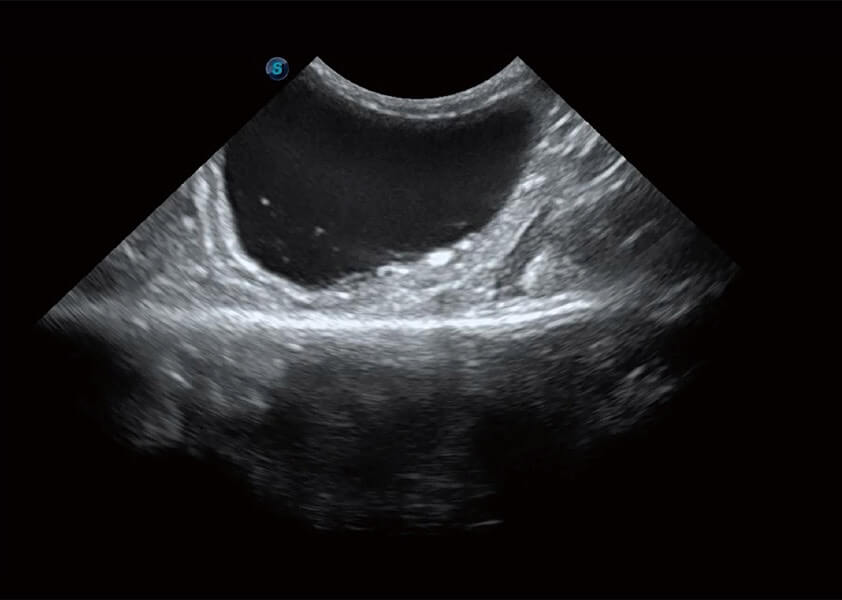

ProPet 60 作为一款高端台式动物超声设备,为动物医生的日常诊断提供了一系列贴合动物临床需求、解决临床实际问题的高级成像功能。凭借全系列高清探头,满足医生对腹部、心脏、生殖、浅表、肌骨等成像的所有需求,切实帮助您提升检查效率,提高诊断信心。

动物是人类最亲密的朋友和最值得信赖的伙伴。诸侯快讯官网也一直致力于探索动物专用的超声影像解决方案。 全新推出的ProPet系列,是诸侯快讯官网在动物超声影像智能化、专业化、精准化的一次跨越式革新。动物不能用言语来表述自己的不适,通过超声影像,ProPet系列搭建了动物医生与不同物种沟通的“桥梁”,为动物医生注入了“治愈之力”。